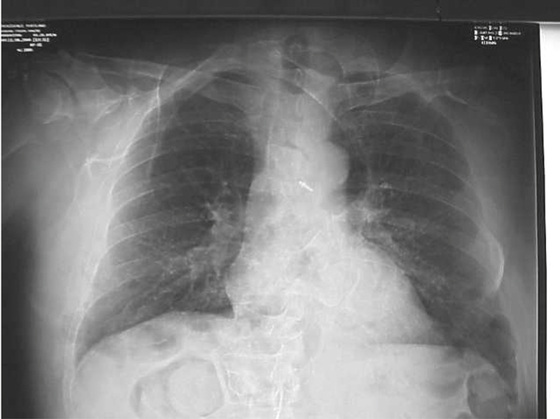

If the x-ray exposure field is not properly collimated, sized, and positioned, exposure field recognition errors may occur. These can lead to histogram analysis errors because signal outside the exposure field is included in the histogram. The result is very dark or very light or very noisy images (Figure 21-15).

Collimation of the projected area x-ray beam is important for patient radiation dose reduction and for improved image contrast in screen-film radiography. In DR, proper collimation has the added value of defining the image histogram. If improperly collimated, the histogram can be improperly analyzed, resulting in an artifact such as that shown in Figure 21-16.